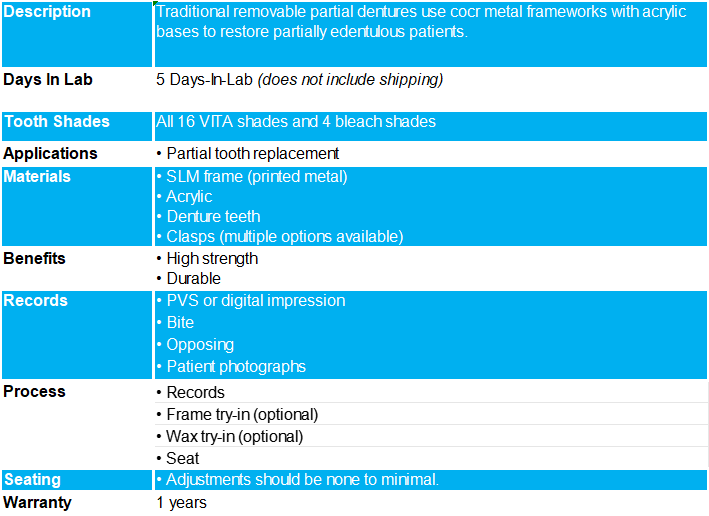

Cobalt chrome framework denture

Cobalt chrome has long been the gold standard for partial denture frameworks due to its:

Exceptional strength-to-weight ratio

Superior biocompatibility, and

Proven clinical performance

Precise design and fit maximize load distribution through natural teeth, preventing tissue compression and damage while enhancing overall denture stability

Exceptional accuracy minimizes chairside adjustments and patient appointments, improving practice efficiency and patient satisfaction

Using laser printing technology